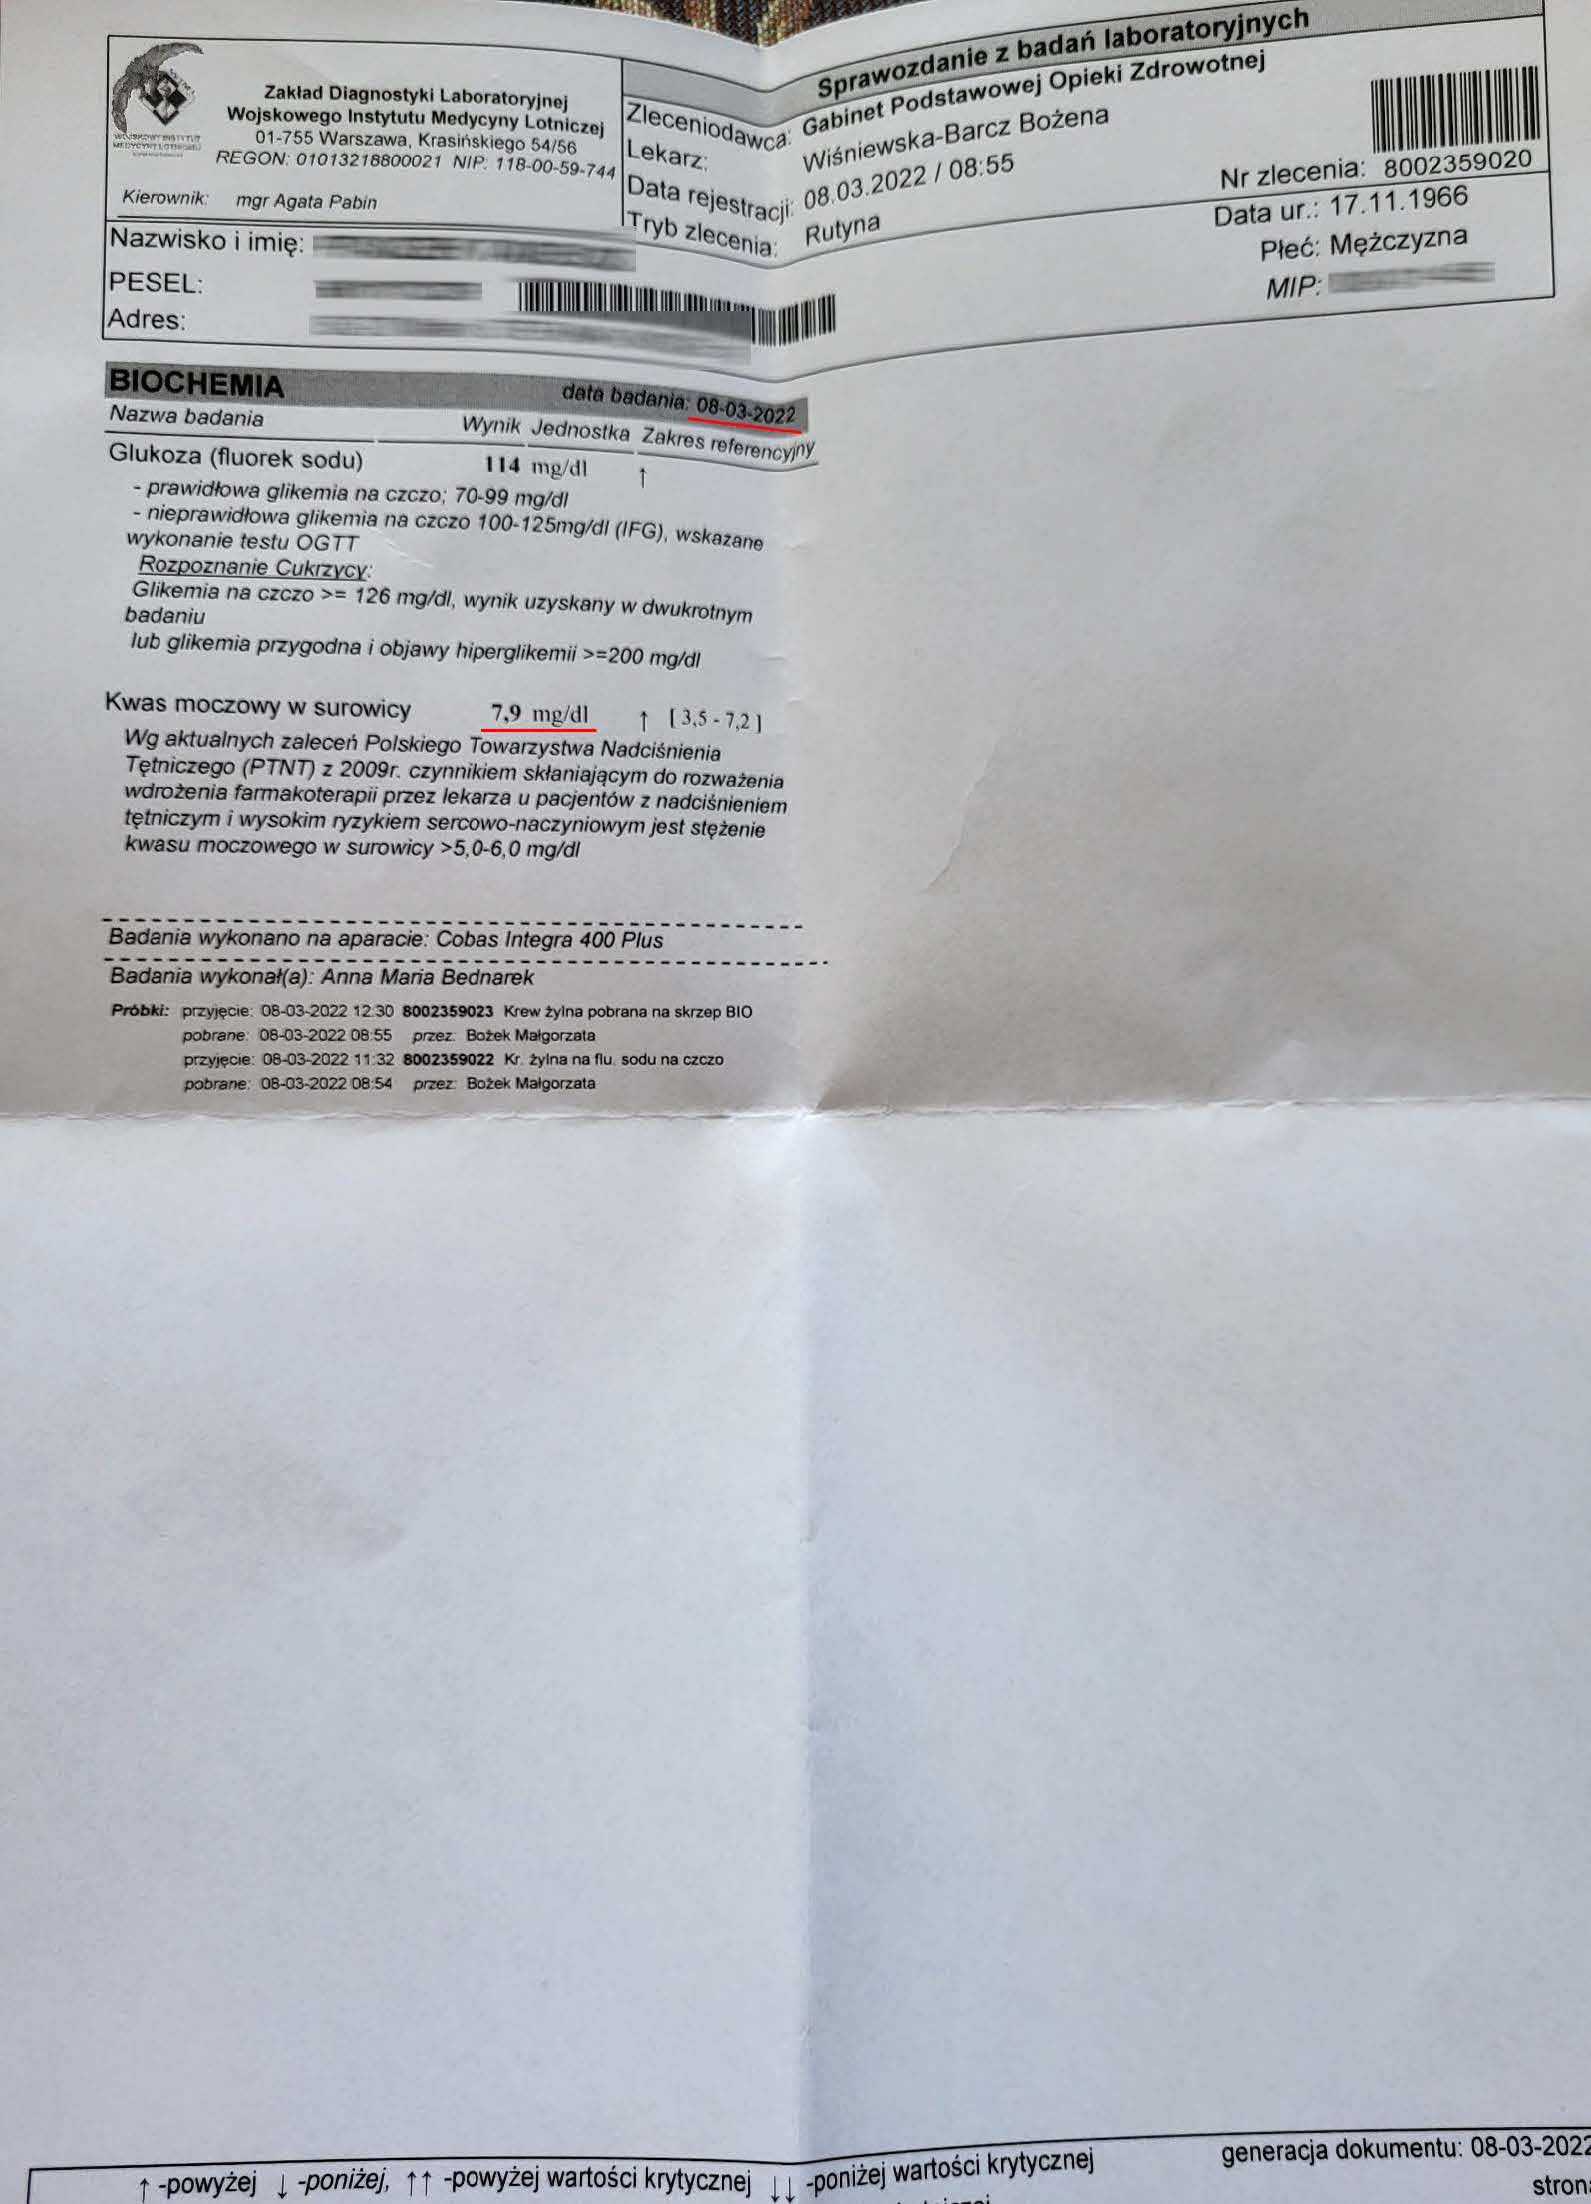

EFEKT PREPARATU NA PODAGRĘ

Dna moczanowa u 56 letniego mężczyzny, diametralny spadek kwasu moczowego. Wartość przed terapią 9,0 mg/dl towarzyszące cykliczne ataki dny , historia choroby zaczęła się jednak znacznie wcześniej niż data pierwszego badania. W roku 2022 rozpoczęto terapię preparatem i po 3 miesiącach stosowania odnotowano spadek kwasu moczowego do 7,9 mg/dl , natomiast po stosowaniu przez następne 6 miesięcy ilość kwasu moczowego obniżona została do poziomu 3,6 mg/dl, wraz z obniżeniem poziomu kwasu moczowego do pożądanego poziomu ustały ataki dny, efekt utrzymuje się trwale. Redukcja o 60% kwasu moczowego pokazuje odwrócenie nagromadzeń moczanowych. Preparat zwiększa ATP mitochondrialny w komórkach nerek i wątroby, poprawiając metabolizm puryn i filtrację, co usuwa kryształy moczanu i wycofuje zapalenie stawów. Standardowe leczenie allopurynolem i kolchicyną wymaga dożywotniego leczenia obarczonego skutkami ubocznymi, które wpływają na codzienne funkcjonowanie, w przypadku preparatu brak skutków ubocznych i relatywnie szybka odpowiedź organizmu.